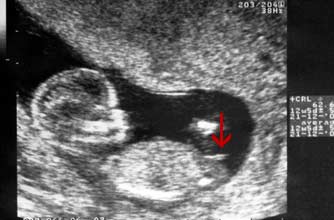

Girl nub: The nub isn't pointing up more than 30 degrees - in fact it's almost horizontal!

小肿块没有指向三十度以上 - 事实上它几乎是水平的!